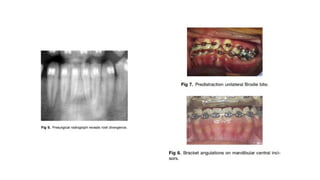

John W. King. Unilateral Brodie bite treated with distraction osteogenesis. (Am J Orthod Dentofacial Orthop 2004;125:500-9)

• A girl, aged 11 years 10 months, was referred by her general dentist for evaluation of her posterior

buccal crossbite.

• Although the patient had the sickle cell anemia trait, she was in excellent physical and dental

health.

• Pretreatment facial photographs showed a convex profile, mildly protrusive lips, and facial

symmetry with competent lips.

• The maxillary dental midline was 1.0 mm to the left of the facial midline; the mandibular dental

midline was 1.6 mm to the left of the facial midline.

• The patient had a Class I malocclusion, 3 mm of overjet, a 75% overbite, and a mild curve of

Spee.

• Both the maxillary and the mandibular arches were symmetrical, with 7.0 mm of maxillary arch

length excess and 5.4 mm of mandibular arch length excess.

• A left posterior buccal crossbite was present, without any lateral shift detected between centric